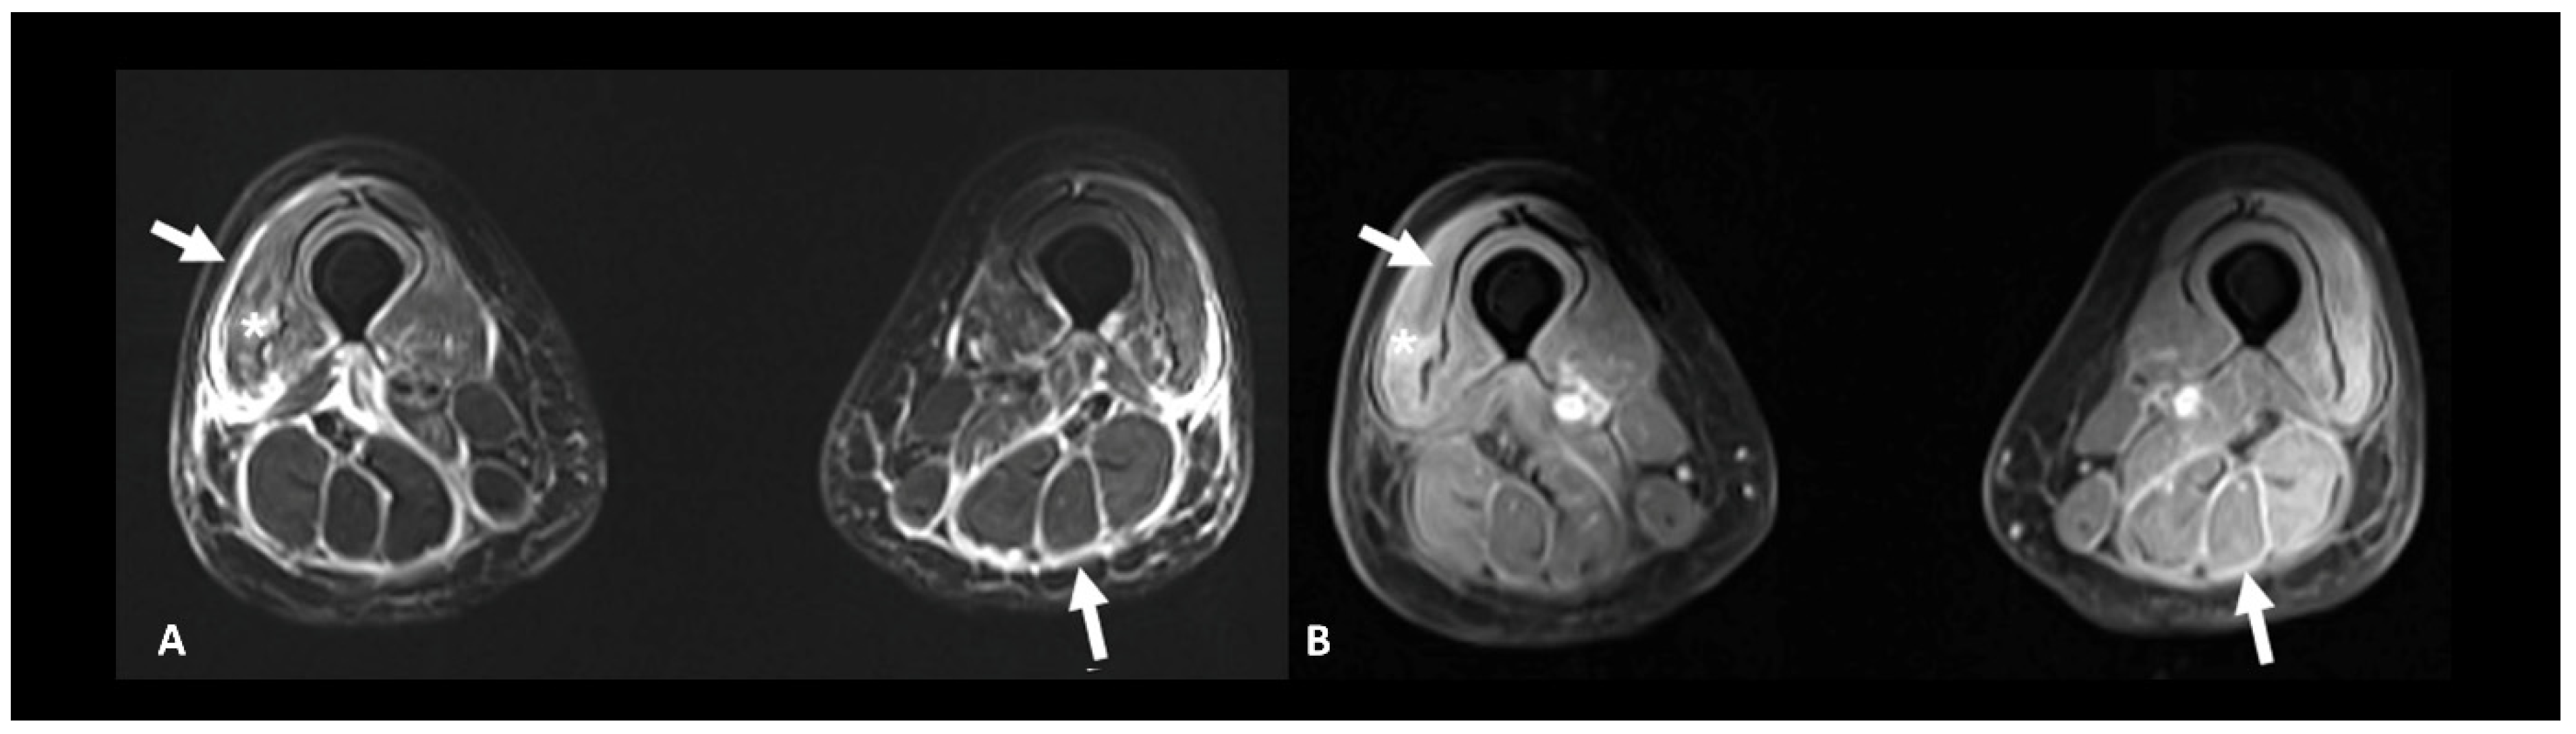

2.6. Ir-Rheumatological and Musculoskeletal Adverse Events

Rheumatic and musculoskeletal toxicities are reported in up to 10% of patients [10]. Myositis, with or without fasciitis, is a rare but severe complication that needs to be ruled out in case of myalgia. MRI is useful to confirm the diagnosis by showing muscle edema (Figure 12). Inflammatory arthritis, including polymyalgia rheumatica, can occur in 5–10% of patients [10]. Ultrasound is the modality of choice to depict synovial hypertrophy, tenosynovitis, articular effusion as well as synovial hyperemia on power Doppler analysis; however, MRI provides a more thorough and less operator-dependent assessment of the inflammatory activity by showing soft tissue and bone marrow edema as well as synovial enhancement [104]. Typically, increased uptake of the articular surfaces is seen at 18F FDG PET/CT, but articular erosions are rarely found in this context.

Figure 12.

Immune-related myositis/fasciitis in a patient with a history of glioblastoma, under antiPD-1. T2 (A) and post-contrast T1 fat-suppressed (B) images show muscle edema with enhancement (asterisks), as well as thickening and enhancement of muscular fascia (arrows) distributed in the anterior and posterior compartments of both thighs. Lesions regressed under steroid therapy.